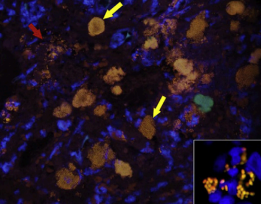

Dt: Hypoalbuminemia, anemia(GI loss), Colon biopsy (inflammation, PAS+ macrophages, FISH: Fluorescence in situ hybridization)